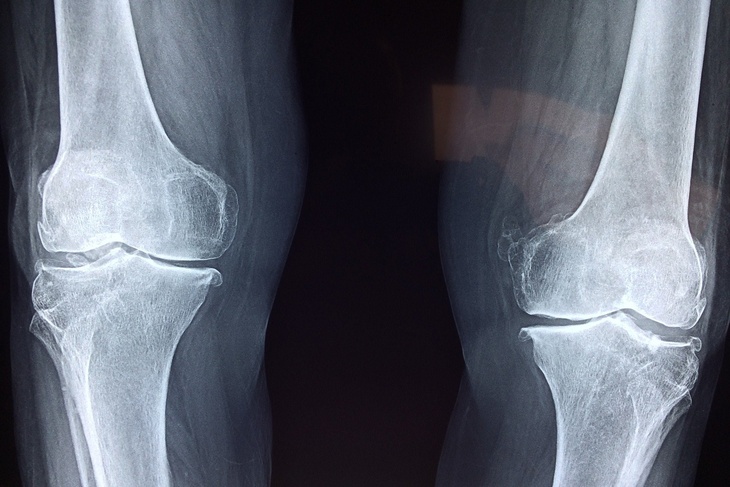

Кроме того, при возрастном снижении плотности костей необходимо принимать препараты с содержанием кальция и других веществ. Женщинам после 50 лет, чтобы снизить риски остеопороза, нужно сдавать анализы на плотность костей. Употребление коллагена также положительно скажется на состоянии связок.